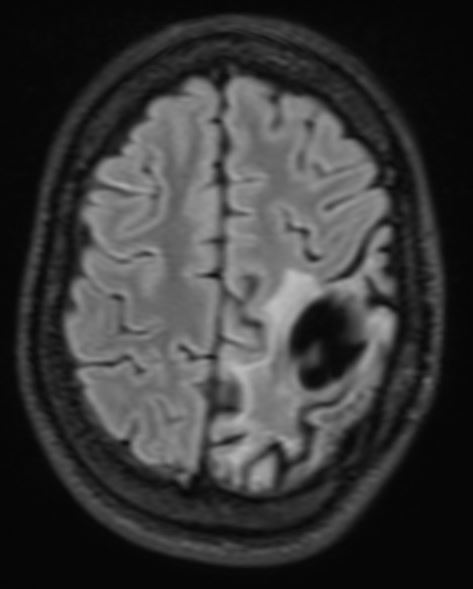

The patient presented with headache and vomiting and subsequently had surgery on three occasions for an intraventricular meningioma, with the following sequelae on MRI scan